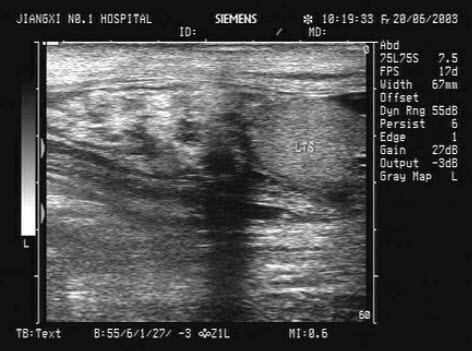

57、单项选择题

患者女36岁,反复上腹部疼痛不适数10年,偶尔皮肤、巩膜黄染。B超检查如图所示,根据超声声像图,诊断为()